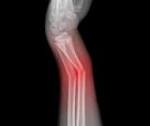

Складчатые переломы предплечья у детей обычно локализуются в области дистального метафиза. Причиной становится падение на ладонь. Клиника скудная. Отмечаются небольшие боли и умеренная припухлость чуть выше лучезапястного сустава. Ощупывание и осевая нагрузка болезненны. Рентгенография лучезапястного сустава подтверждает диагноз. В трудных случаях назначают МРТ или КТ лучезапястного сустава. Лечение проводят в травмпункте. На руку накладывают гипс на 2 нед. Потом назначают ЛФК.

Эпифизеолиз дистального отдела лучевой кости - самая распространенная травма в группе переломов предплечья у детей. Эпифизеолиз луча может быть изолированным либо сочетаться с отрывом шиловидного отростка или с эпифизеолизом локтевой кости. Клиническая картина часто недостаточно четкая. В области лучезапястного сустава появляется припухлость и болезненность, которые родители иногда расценивают, как последствия ушиба. При значительном смещении симптомы выражены более ярко - возникает значительный отек, деформация и резкая боль.

Рентгенография лучезапястного сустава позволяет уточнить диагноз. Лечение осуществляется в травмпункте детским травматологом. При необходимости проводят репозицию и накладывают гипс на 3-4 нед. Затем направляют ребенка на ЛФК.